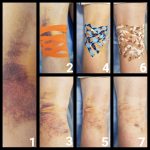

Czym jest kinesiotaping czyli plastrowanie dynamiczne to metoda terapeutyczna polegająca na oklejaniu fragmentów ciała plastrami o specjalnej strukturze. Jest to jedna z metod tapingu (naklejania plastra). Przy tej metodzie wykorzystuje się specjalny plaster – Kinesio Tex, który nie ogranicza ruchów, a jego elastyczność wynosi 130%–140%. Sposób nacięcia zależy od miejsca aplikacji i przypomina wachlarz lub litery X, Y, I.

Plaster rozciąga się wyłącznie na długość, nie zawiera leków ani lateksu, jest wodoodporny i pozwala skórze oddychać dzięki falowej strukturze.

Taping, czyli plastrowanie, to naklejanie rozciągliwego plastra. Plaster jest źródłem bodźców mechanicznych, nie jest nasączony żadnym lekiem. W zależności od miejsca aplikacji ma różne oddziaływanie – plastrowanie stosuje się w celu zmniejszenia bólu oraz obrzęku, przyspieszenia procesu gojenia, korekcji mechanicznej, poprawy stabilizacji m.in. przy bólach kręgosłupa, kolana czy barku.

Plastrowanie dynamiczne likwiduje obrzęki limfatyczne poprzez poprawę krążenia krwi i chłonki, zmniejsza zatory tkankowe i stany zapalne oraz otwarcie drenażu limfatycznego pod skórą. Plastry pomagają również w korekcji stawów.